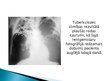

Ja ārstam ir aizdomas par tuberkulozes infekciju, vispirms tiek izdarīts plaušu rentgens un krēpu analīze.

Plaušu rentgens ir vienkārša un laba metode, kā noteikt vai slimniekam ir plaušu tuberkuloze vai nav.